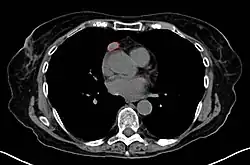

![]() Un timoma encapsulado (de tipo linfocítico y epitelial combinado). | ||

Del 30 al 50% de las personas con un timoma no tienen síntomas, y la masa es identificada de manera incidental en una radiografía de tórax o en una tomografía computarizada (TC).[1]

Ante la sospecha de un timoma, generalmente se realiza una TC para valorar el tamaño y extensión del tumor, a este se le puede tomar una muestra a través de una biopsia guiada por radiología. El realce vascular incrementado en la TC puede ser indicativo de malignidad, así como la presencia de derrame pleural.[1] La toma de biopsia está asociada con un pequeño riesgo de neumomediastino o mediastinitis e incluso un riesgo aún menor de daño cardíaco o a los grandes vasos. Algunas veces el timoma puede tener metástasis en el abdomen.[6]